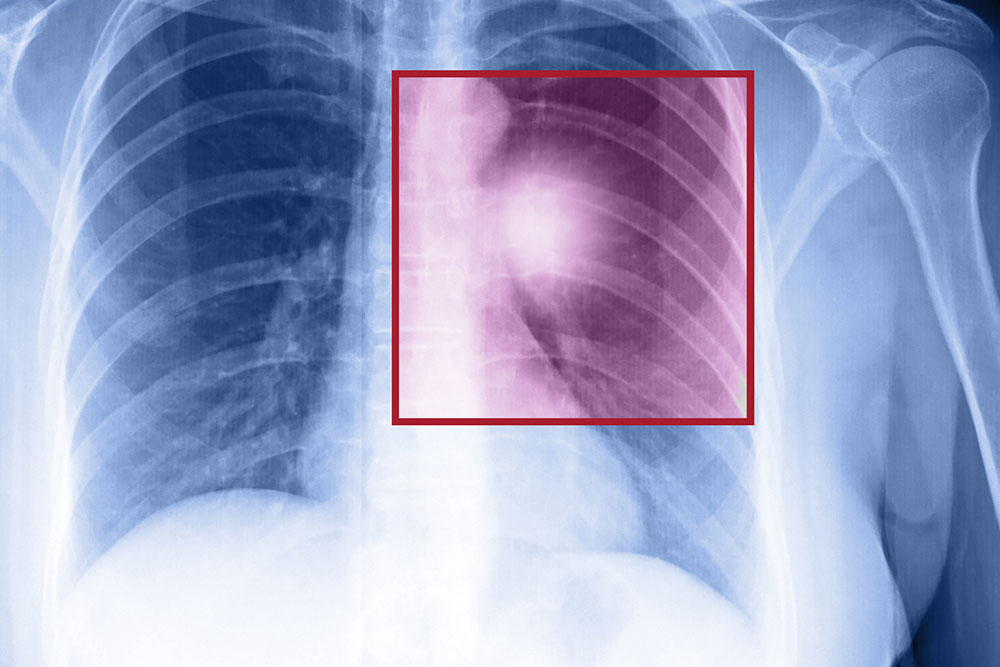

Metastatic lung cancer may not always show up in signs and symptoms. Even when you do start experiencing the symptoms, it may be quite difficult to identity this form of lung cancer, because the symptoms are similar to several other medical conditions. Some of the symptoms of metastatic lung cancer include chest pain, weakness, a persistent cough, wheezing, shortness of breath, coughing up blood, and sudden weight loss. If your doctor suspects metastatic lung cancer, you may have to take various tests to confirm the diagnosis of metastatic lung cancer. These tests are a bronchoscopy, a CT scan, a chest X-ray, and a lung needle biopsy.